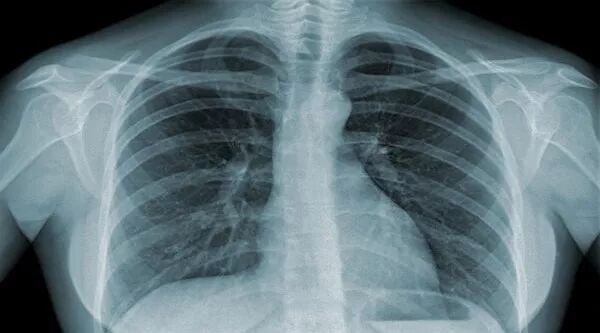

肺癌示意图

利亚·史密斯指出,肺癌发病率在过去几十年中一路下降,同时男性患肺癌的比例及肺癌死亡率比女性下降得更快,这要归功于加拿大近年来展开的大规模戒烟教育活动。加拿大癌症协会的报告最后表示,接近一半的加拿大人都会在一生中的某个阶段被诊断患上癌症……虽然存活率大大提高,但情况仍不容乐观。新华网曾于去年刊登文章,介绍了中国癌症患者的总体存活率:“国家癌症中心统计数据显示,我国每年新发癌症病例超350万,死亡病例超200万;肺癌、乳腺癌、胃癌等是最常见的癌症……研究显示,我国总体癌症5年生存率为30%左右,较发达国家仍有不小差距。”据北京晨报,谈及我国肿瘤5年生存率不足发达国家一半的原因。长期从事肿瘤病因即癌变机理研究的程书钧院士表示,造成这样的原因是多方面的。其中最重要的原因是我国相当一部分肿瘤患者处于中晚期,到医院治疗时,肿瘤已经发生转移,很难治愈了。此外,人民日报对“为什么越来越多的年轻人患上癌症?”做过总结: